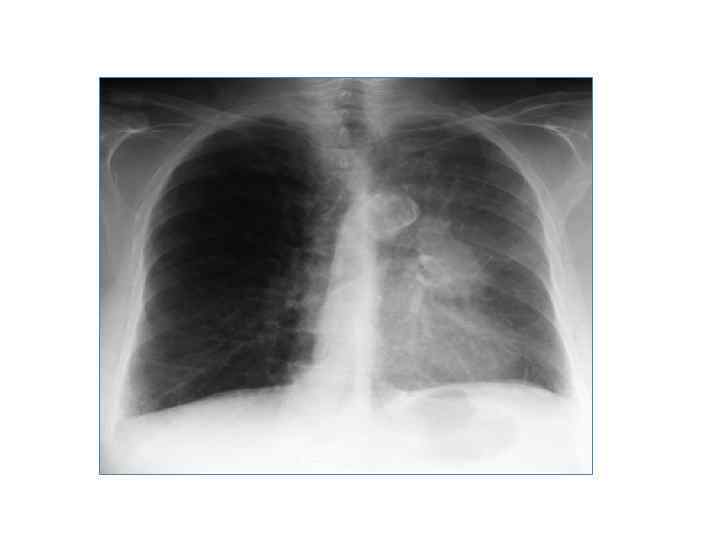

Аденокарцинома 25 -30% всех случаев немелкоклеточного рака. Солитарное периферическое образование (редко – в крупных бронхах). Размеры небольшие (менее 4 см). Округлая или овальная форма. Относительно четкие и ровные контуры. Обызвествления – 4 -6% случаев. Метастазы: ЛУ корня легкого у 20% больных на момент выявления.

Плоскоклеточный рак 20 -25% всех случаев немелкоклеточного рака. Медленно растущая опухоль. Размеры различные (. . . мм до 8 -10 см). Чаще поражаются крупные бронхи. Ателектаз, обтурационный пневмонит при центрально расположенных опухолях. Распад опухоли – 10 -20%. Метастазы: ЛУ, кости, надпочечники.

Крупноклеточный рак 10 -20% всех случаев немелкоклеточного рака. Периферическое образование Обычно крупных размеров (в среднем 7 см) Нечеткие размытые контуры Кальцификация и полости распада – редко Быстрый рост Обширное лимфогенное и гематогенное метастазирование.